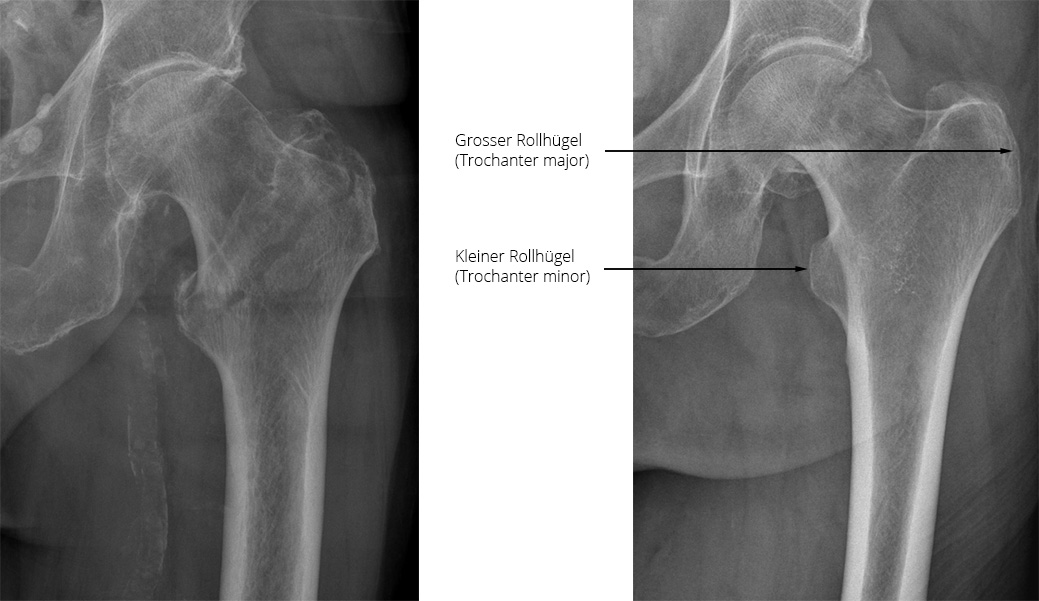

Bei Frakturen des Oberschenkelknochens (Femur) treten am häufigsten die Schenkelhalsfraktur (am Übergang vom Oberschenkel zum Hüftkopf) und die sogenannte pertrochantäre Fraktur (zwischen dem grossen und kleinen Rollhügel) auf. Die Schenkelhalsfraktur liegt nah am Hüftgelenk, innerhalb der Gelenkkapsel. Die pertrochantäre Fraktur hingegen verläuft etwas weiter seitlich, zwischen dem grossen und dem kleinen Rollhügel und verläuft damit ausserhalb der Gelenkkapsel.

Bild: Universitätsklinik Balgrist